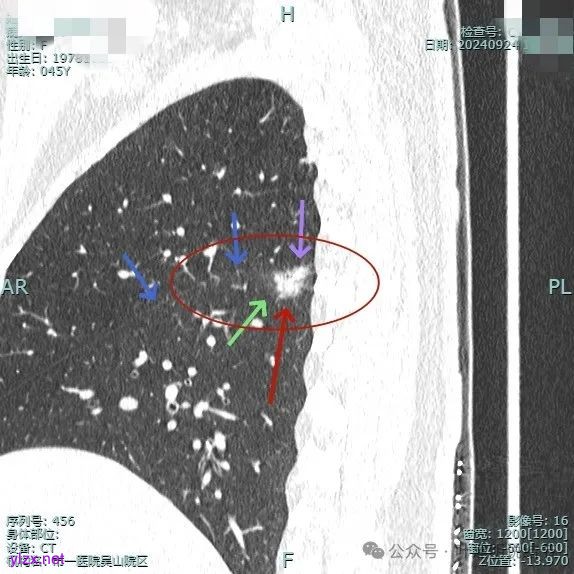

我们先来看2024年9月时的影像:

病灶3:

病灶混合密度,但瘤肺边界不够清楚,灶内也不太致密。

整个显得有点模糊,虽有血管进入,但血管说不上显著异常增粗,病灶边缘有细毛刺,贴胸膜近,但缺乏明显收缩力。

病灶显糊,轮廓较清但瘤肺边界欠清晰。

有血管进入,但病灶的感觉总好像缺乏收缩力,也聚拢性不太够。